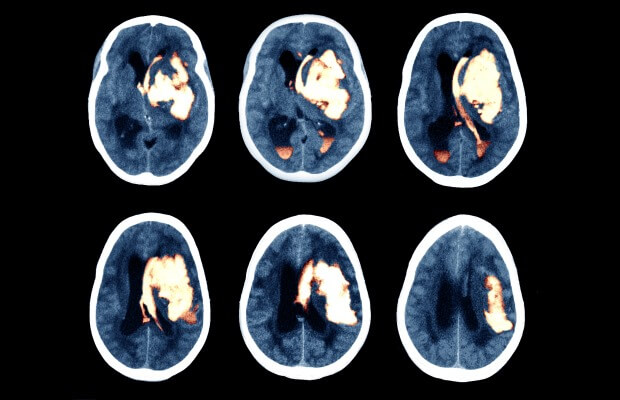

An MRI scan, showing the brain